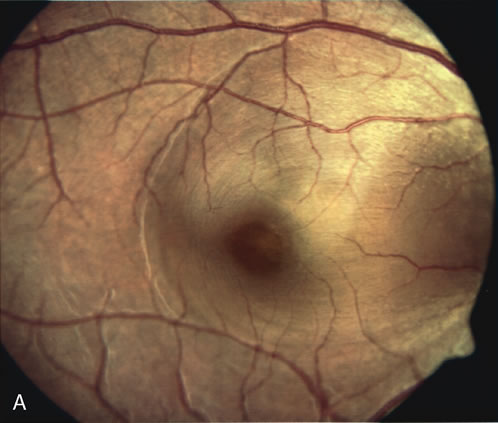

DIAGNOSIS In general, the diagnosis of a macular hole is readily made in patients who present clinically with a full-thickness retinal defect, yellow exudative deposits at the base, and, occasionally, an operculum. However, it is sometimes difficult, using contact lens biomicroscopy alone, to distinguish a full-thickness macular hole from simulating conditions. Visual acuity is often 20/200 to 20/400 in an eye with a full-thickness hole, whereas eyes with macular cysts or pseudoholes usually have better vision. Visual acuity, however, cannot rule in or rule out a full-thickness macular hole.213,214 The differentiation of a partial-thickness, or lamellar, macular hole from a full-thickness macular hole can be challenging, and FA is often helpful in assisting in the diagnosis.55 As in a full-thickness hole, a lamellar hole presents as an excavation of the retina, and the presence of drusen underneath the lamellar hole can simulate the yellow deposits seen at the base of full-thickness holes. Occasionally, there is a full-thickness hole at one side of a lesion, and the rest of the lesion consists of a lamellar defect. FA will show immediate hyperfluorescence from the choroidal circulation under a full-thickness hole (Fig. 34A), whereas a lamellar hole, with a relatively intact RPE, will block some of the normal fluorescence from the choriocapillaris (Fig. 34B).